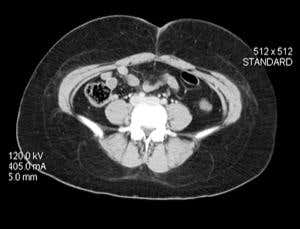

Big job (Image: Living Art Enterprises, LLC/Science Photo Library)

To get a clear picture when performing a CT scan on someone with obesity, radiologists usually need to use a higher dose of X-rays than they would give someone of average weight. What effects, if any, does this have on health?